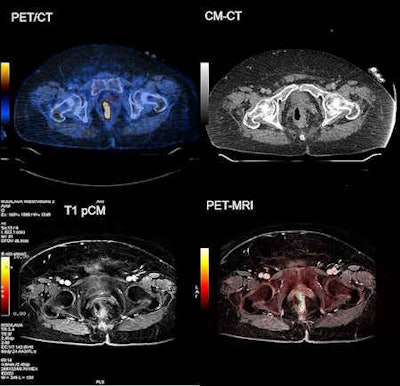

For prostate imaging, the combination of PET/CT-MRI can serve as a one-stop imaging tool for patients who need staging and restaging. The images provide information about the local tumor status, nodal status, and distant metastases.

"We always coregister the PET/CT images with the MRI data using a commercially available imaging workstation (Advantage Windows, GE Healthcare). The MRI exam is typically performed as a whole-body examination due to current research trials comparing PET/CT and PET-MRI. It also may be a partial-body contrast-enhanced examination of the abdomen, pelvis, head/neck, or brain," Veit-Haibach said.